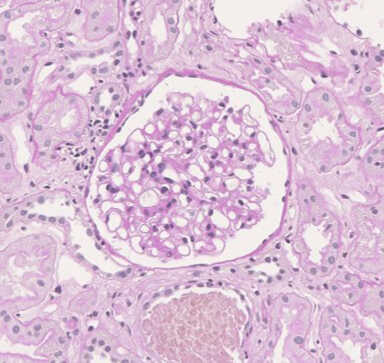

Histological Staining of Human Kidney Biopsy Samples

Data by courtesy of Dr. Furuhashi, Department of Nephrology, Nagoya University Graduate School of Medicine

Kidney tissue was collected using a 16 G biopsy gun and fixed with FM Fix (s) for one day at 4°C. After paraffin embedding and sectioning, hematoxylin and eosin (HE), periodic acid-Schiff (PAS), periodic acid-methenamine-silver (PAM), and Masson’s-trichrome (MT) staining were performed.

PAM

![[PAM] 10% Neutral buffered formalin](images/03340_img09.jpg)

![[PAM] FM Fix (s)](images/03340_img10.jpg)

[Result]

Tissue structure was better preserved with FM Fix (s) than with 10% neutral buffered formalin.